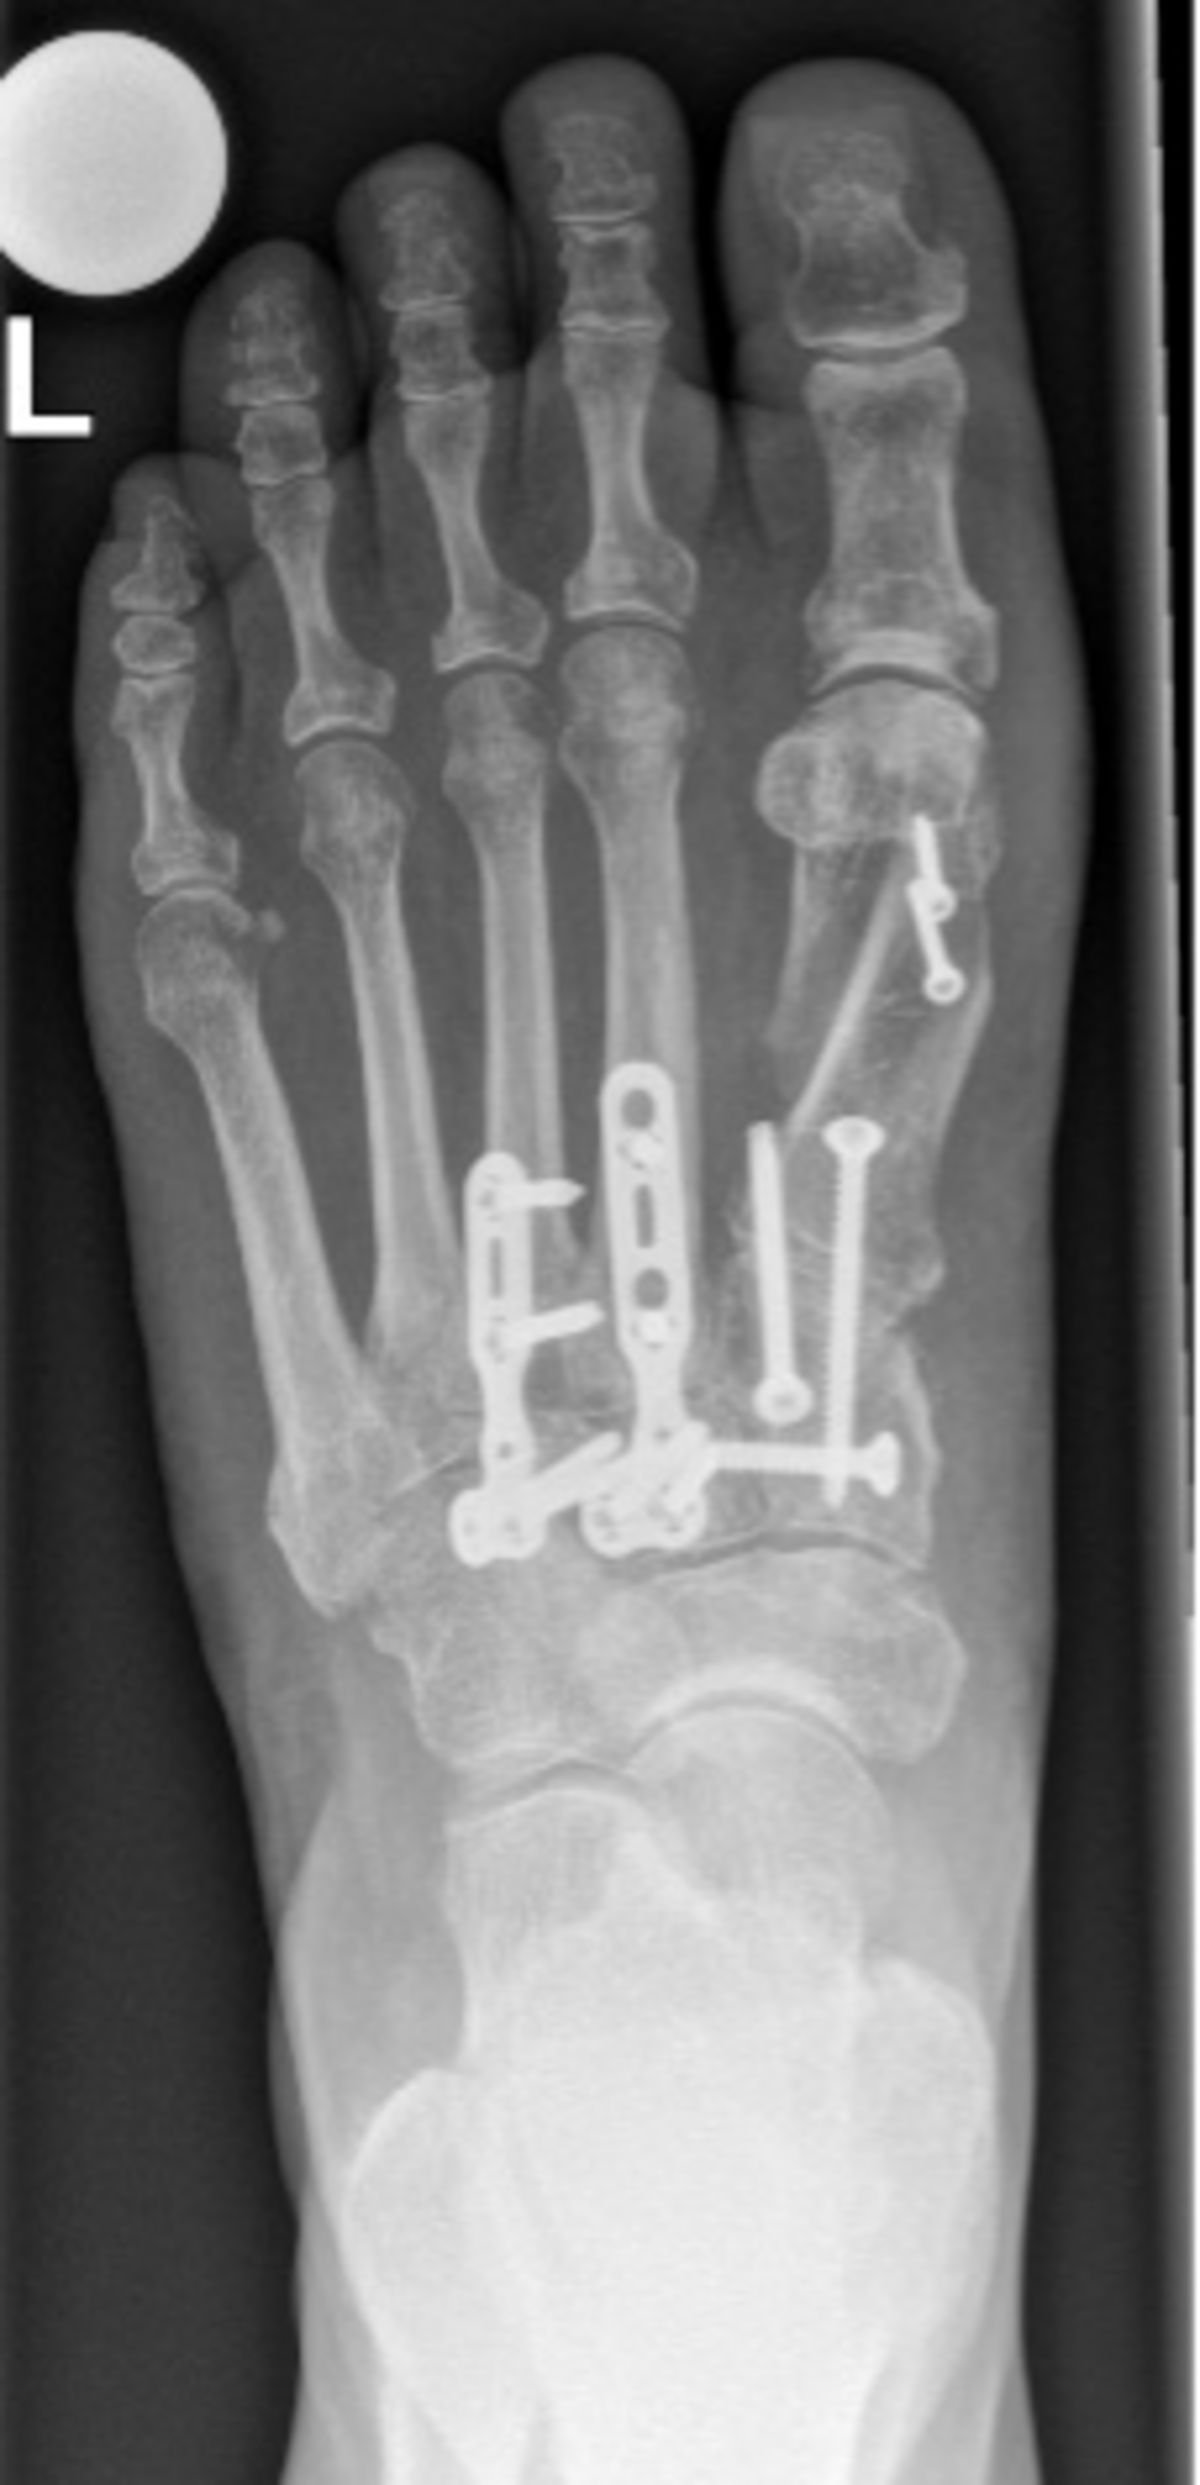

Bild: Universitätsklinik Balgrist

Führt die konservative Therapie nicht zum Erfolg, kommt eine Operation in Frage. Bei störenden Osteophyten und nur geringfügiger Arthrose kann ein Abtragen des Knochens zum Erfolg führen. Ist die Arthrose fortgeschritten, fällt die Wahl meistens auf eine Versteifung (Arthrodese). Die betroffenen Gelenke werden dazu durch Schrauben oder Platten fixiert. Da die Mittelfussgelenke wenig zur Gesamtbewegung des Fusses beitragen, ist der Einfluss der Versteifung auf den Bewegungsumfang des Fusses gering. Dadurch ist gehen auch nach der Versteifung weiterhin gut möglich.